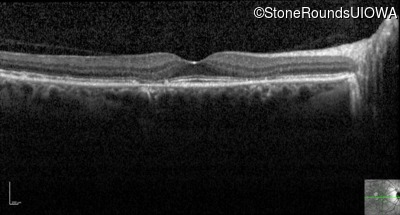

Optical Coherence Tomography - Right - 20/20

Exemplar / OCT Stack

OCT Stack